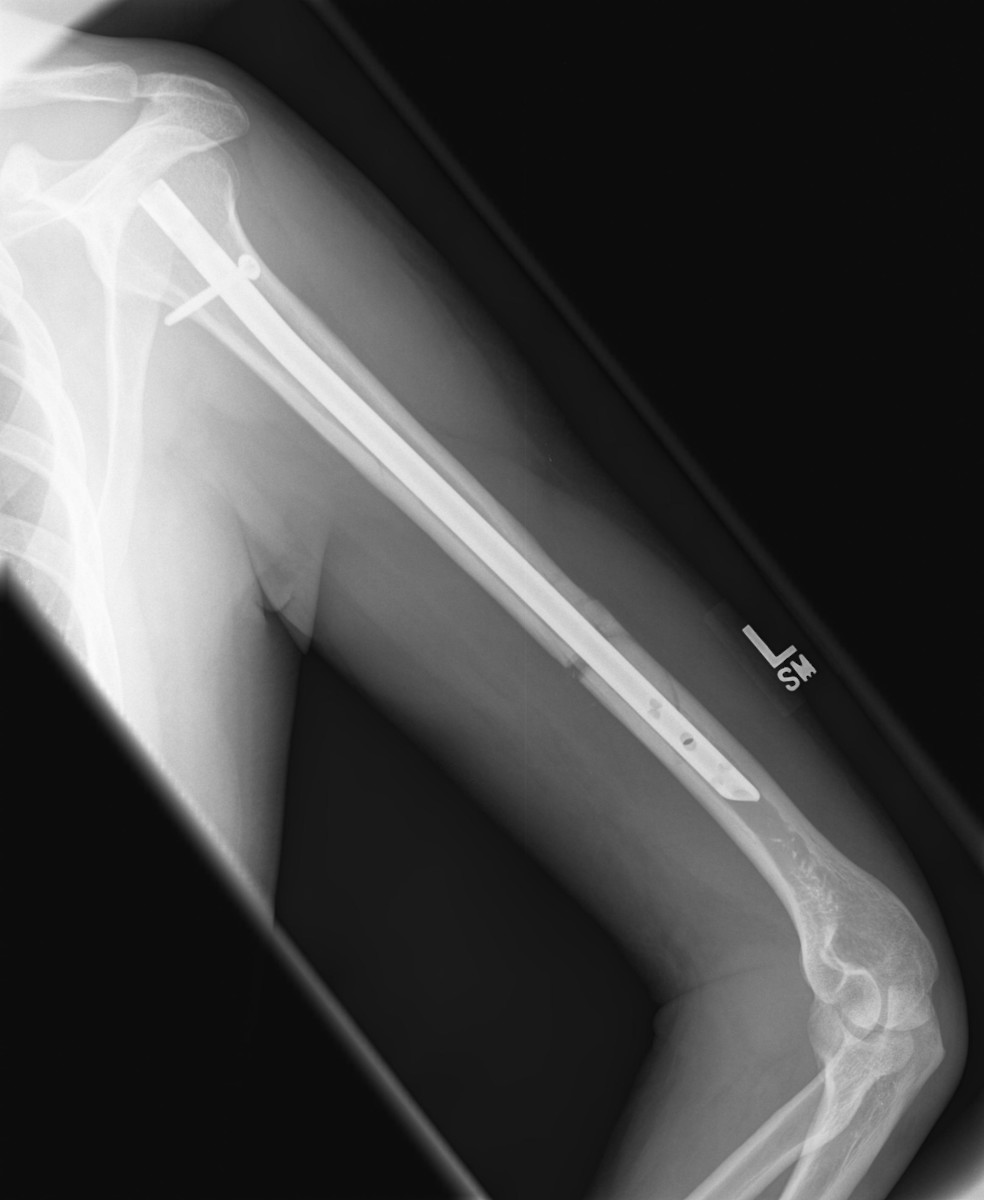

A Broken Humerus — Road to Recovery Maddie Wirthman Medium How To Shower With A Broken Humerus I recently fractured my left humerus and found that reading humerus fracture recovery blogs has been helpful in anticipating the healing process. There are two main approaches that your surgeon may use: During the first four weeks it is. In this video the surgeons discuss shoulder fractures. Shampoo and conditioner in basket at. They discuss the mechanism of injury, the.. How To Shower With A Broken Humerus.

A Broken Humerus — Road to Recovery by Maddie Wirthman Medium How To Shower With A Broken Humerus Wear the sling all the time, only removing it to regularly exercise your arm, and to shower. They discuss the mechanism of injury, the. Try to do this every 1 to 2 hours for the. Shampoo and conditioner in basket at. During the first four weeks it is. In this video the surgeons discuss shoulder fractures. If you have an. How To Shower With A Broken Humerus.